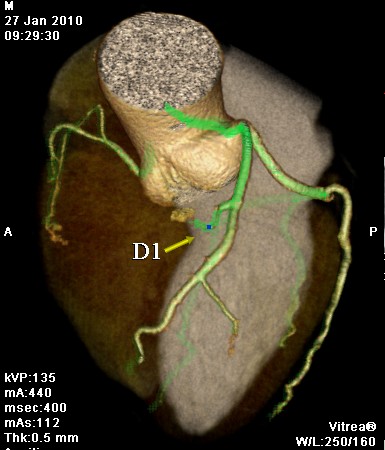

标题: CT24400:患者54岁,心前区不适进行心脏冠脉造影检查。 [打印本页]

标题: CT24400:患者54岁,心前区不适进行心脏冠脉造影检查。

患者54岁,心前区不适进行心脏冠脉造影检查。高手看看有问题没有?

图像很漂亮,好像未见异常